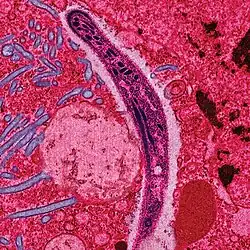

Men spreekt over een infectie als een micro-organisme, virus, prion of parasiet in een levend wezen is binnengedrongen en zich daar vermenigvuldigd heeft (dit hoeft niet schadelijk te zijn). Wanneer het organisme dusdanig veel weefselschade aanricht dat het normaal functioneren van de gastheer is verstoord, spreekt men van een infectieziekte. In het ergste geval kan een infectie leiden tot de dood van het geïnfecteerde individu. Het micro-organisme wordt bij een ziekmakende infectie het pathogeen, de ziekteverwekker genoemd. Als de ziektekiemen zich nog niet hebben vermenigvuldigd, of als ze door het immuunsysteem worden herkend en verwijderd, spreekt men niet van een infectie maar van besmetting.

Een infectie ontstaat als een pathogeen invasief wordt, het bloed of weefsels binnendringt. Een toxi-infectie is een infectie waarbij de pathogenen giftige stoffen afscheiden, zelfs als de pathogenen zelf niet in het lichaam binnendringen. Voorbeeld: wanneer een gewone huidbacterie op een plek in het lichaam wordt gebracht die normaal steriel is, kan die daar ongebreideld groeien en een enorme last voor de gastheer veroorzaken. Voorbeeld: puistjes, de Staphylococcus aureus veroorzaakt een hevige haarfollikel-infectie.

Bij een virale infectie stelt men meestal een sluipend verloop vast, bij bacteriële infecties is het verloop eerder acuut. Het kan bij infectie met toxoplasmose wel degelijk gebeuren dat er sprake is van chronische processen.